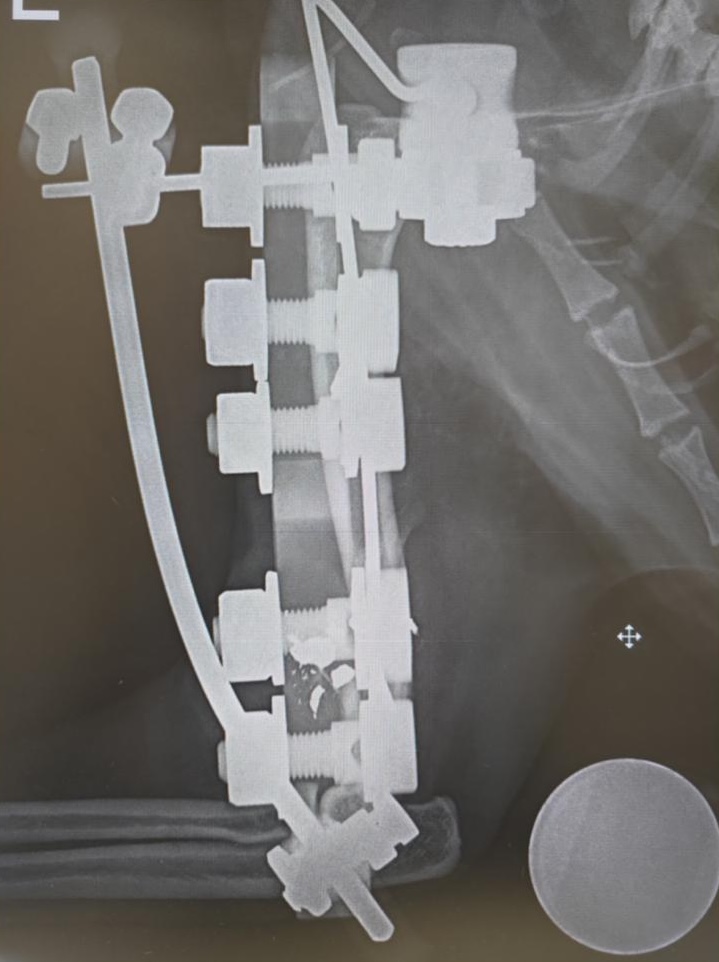

Nel caso della prima gatta il colpo ha lesionato gravemente l’osso di una zampetta ed è stato necessario fare ricorso a una placca, una sorta di protesi, attraverso una delicata operazione. L’altra gatta ferita, oltre che nelle zampette, presentava pallini anche nel resto del corpo. Sono state entrambe operate e sembra che le loro condizioni facciano ben sperare per una ripresa. Purtroppo è l’ennesimo episodio di maltrattamento di questo genere che si riscontra nell’Aretino, dove sono stati segnalati diversi casi di gatti impallinati, in alcuni anche con esito letale.

La protesi che è stata applicata